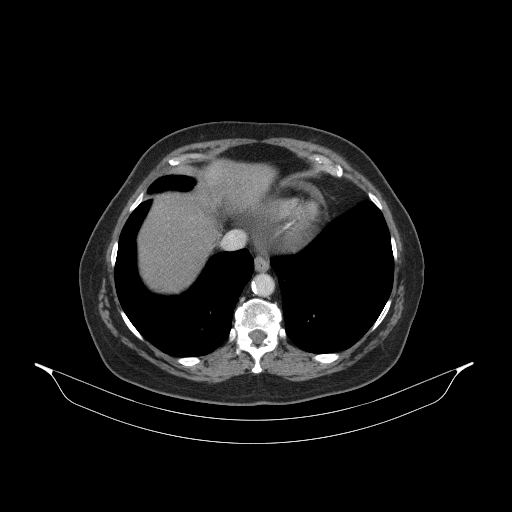

Image Grid

4Γ—3 grid: Rows show different image types (Original NATIVE, Reconstructed NATIVE, Original VENOUS, Generated VENOUS), Columns show windowing techniques (No Window, Lung Window, Mediastinum Window)

Generated VENOUS CT scan (A→B translation)

Mediastinum window (WL 40, WW 400 β†’ Low βˆ’160, High +240)

Actual HU range: [-160.0, 240.0]